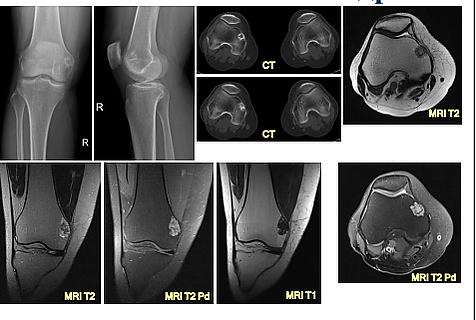

Данный подтип хондромы появляется из кости и растет в сторону мягких тканей. Мягкие ткани при этом процессе уплотняются, в них обнаруживаются участки обызвествления.

Границы экхондромы обнаруживаются с трудом[4].